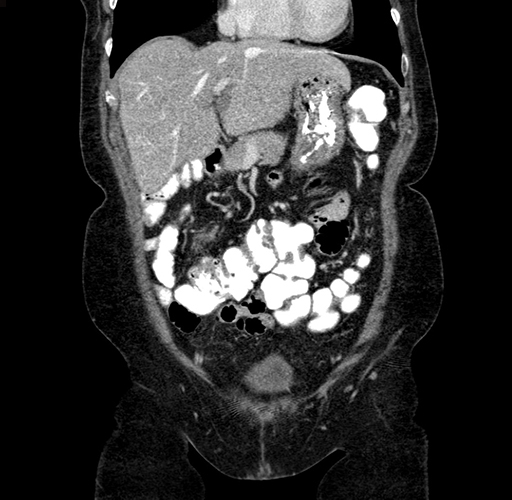

Axial Venous

Coronal Venous